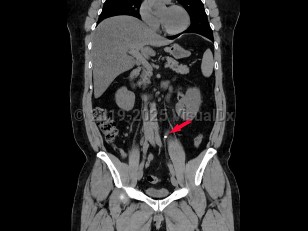

Ureteral calculus

While many stones located within the renal pelvis are discovered incidentally on radiographic or sonographic imaging, most stones that have passed into the ureter and are of significant size cause renal colic. Renal colic is sudden-onset flank pain radiating to the groin, accompanied by nausea and vomiting. This colicky pain typically waxes over the course of 15-30 minutes and becomes steady, unrelenting, and unbearable. Patients may experience worsening paroxysms of pain lasting 20-60 minutes as the stone courses downward through the ureter and as the ureter spasms.

If the stone's descent is arrested at the ureterovesical junction, patients may experience urinary frequency, dysuria, and urgency and are predisposed to the development of urinary tract infections both from the stone forming as a nidus for bacterial growth and from the mechanical urothelial trauma caused by the stone's movement. Most individuals with nephrolithiasis will also develop hematuria, particularly when passing a stone.

Pain from nephrolithiasis is thought to primarily be the result of renal capsular distention and varies depending on the location of the stone and the degree of obstruction caused by the stone. Stones that occlude the upper ureter or ureteropelvic junction invariably cause significant flank pain that is accompanied by severe costovertebral angle tenderness to palpation. As the innervation of the testicle is shared with the kidney, patients often describe radiation to the testicles or labia. When stones pass into the bladder, patients usually experience swift resolution of their pain.